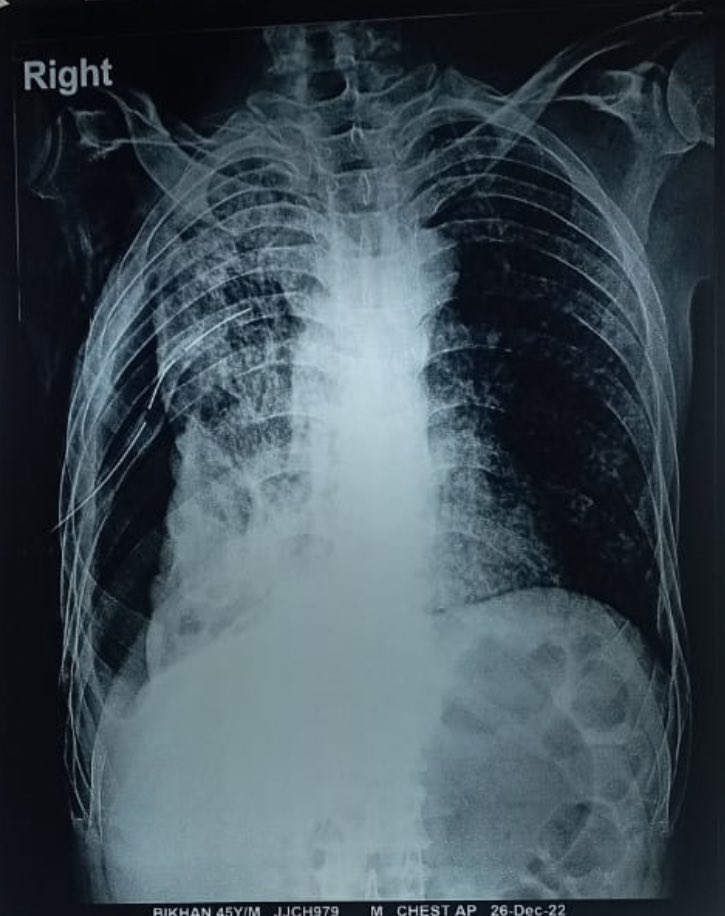

This is quite bad disease and right lung look half fibrosed 🫠 Image

* Final diagnosis: Chronic suppurative lung disease-Right lung Pyo-pneumothorax.

* Probable etiology: Mycobacterium Tuberculosis/Aneeobic bacteria.

On repeating 🩻 it was even 😞 with poor 🫁 expansion and the drain still showing dark pus🫢 Image

CT ruled out cancer looking lesions but showed miliary pattern in the left 🫁 along with a thick walled R middle lobe cavity with a communication to the pleural space. Image